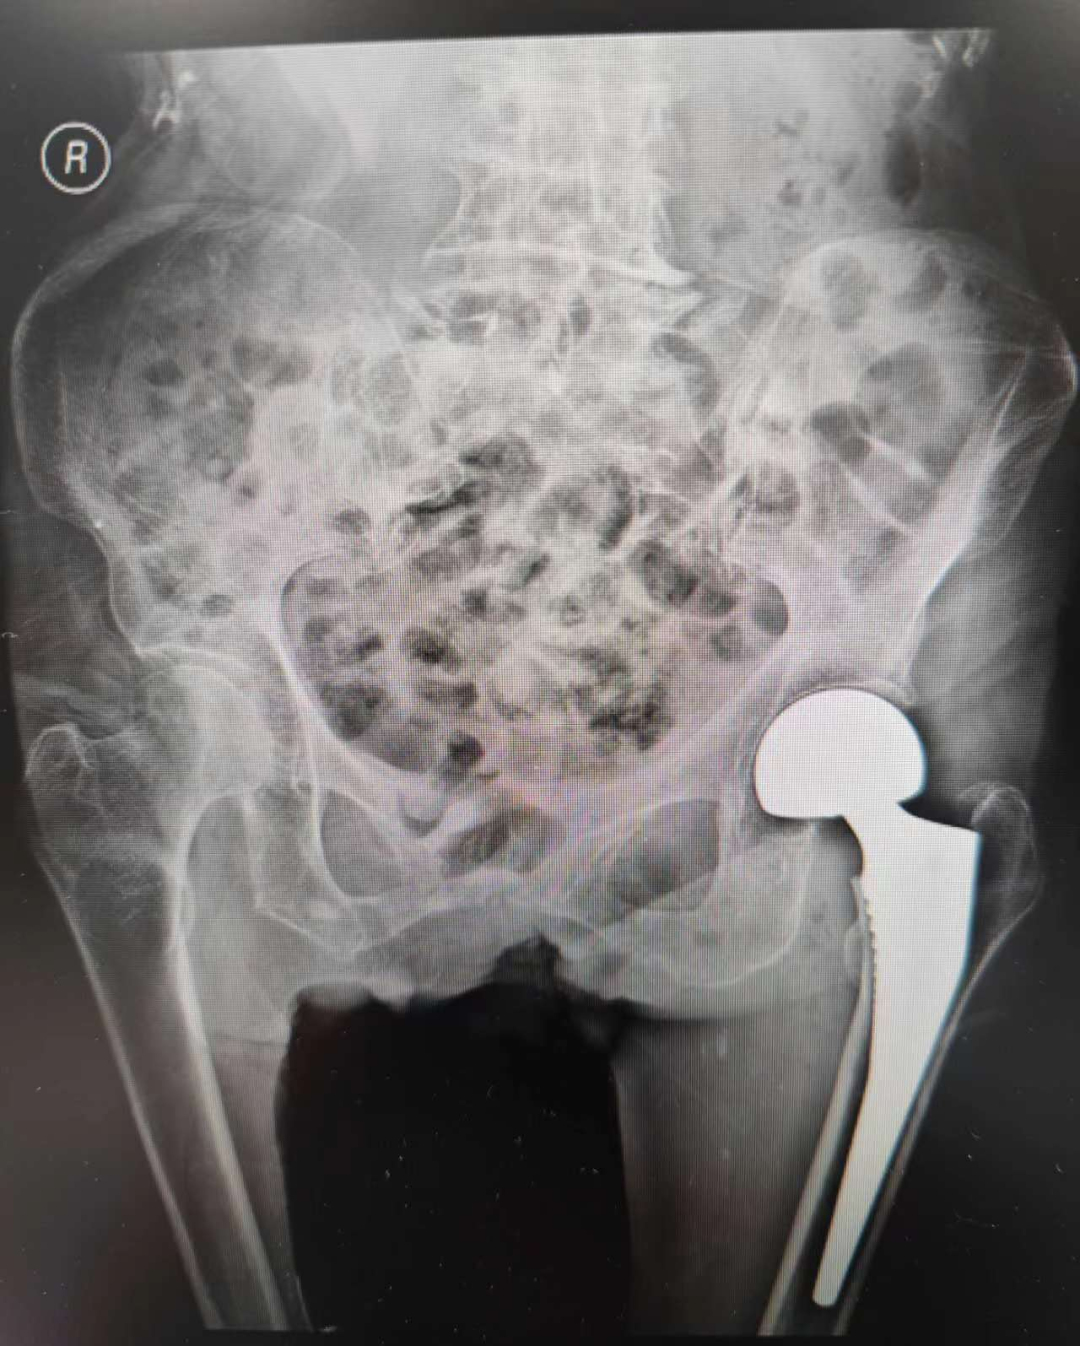

无独有偶,同一天髋关节二科杨小平主任医师手术团队也为另一位百岁患者黄奶奶做了人工关节置换手术,患者也是既往有高血压病史多年。入院诊断:1、右股骨颈骨折;2、高血压病3级 很高危组;3、2型糖尿病;4、腔隙性脑梗死;5、老年性心脏瓣膜病;6、老年性骨质疏松症;7、高血脂病;8、慢性胃炎。在椎管内麻醉下行右股骨颈骨折切开半髋关节置换术,手术半小时顺利完成,术中出血约150ml。黄奶奶术后第1天即可在家属辅助下坐起,第3天在助行器辅助下站立行走。近年来,该科做100岁老人的人工关节置换手术超10例。且效果良好。

▲术后拍片